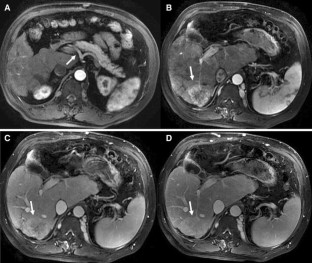

Hepatocellular Carcinoma in Budd-Chiari Syndrome: Enhancement Patterns at Dynamic Gadolinium-Enhanced T1-Weighted MR Imaging

The objective of this study was to analyze the enhancement patterns at dynamic gadolinium-enhanced T1-weighted MR imaging in patients of Hepatocellular Carcinoma (HCC) with associated Budd-Chiari syndrome (BCS). The MR imaging findings in 10 patients of HCC with associated BCS were compared to those of 32 other patients of HCC without BCS. During the arterial phase, significantly more lesions with BCS were hyperintense than lesions without BCS; during the equilibrium phase, significantly more lesions with BCS were slightly hyperintense or isointense than lesions without BCS (P < 0.05 for both). For HCC, contrast enhancement on MRI shows different enhancement patterns between patients of HCC with associated BCS and those without BCS.

Fig. 2